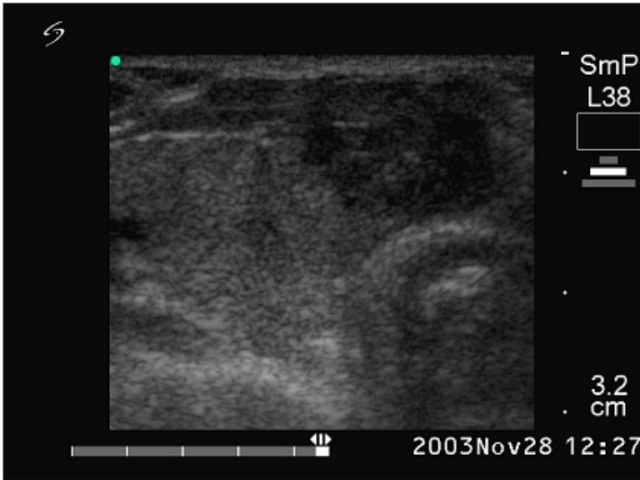

Ultrasonography: echonormal thyroids with two nodules close to each other in the isthmus. They were hypoechogenic inhomogeneous and exhibited irregularly increased intranodular blood flow.